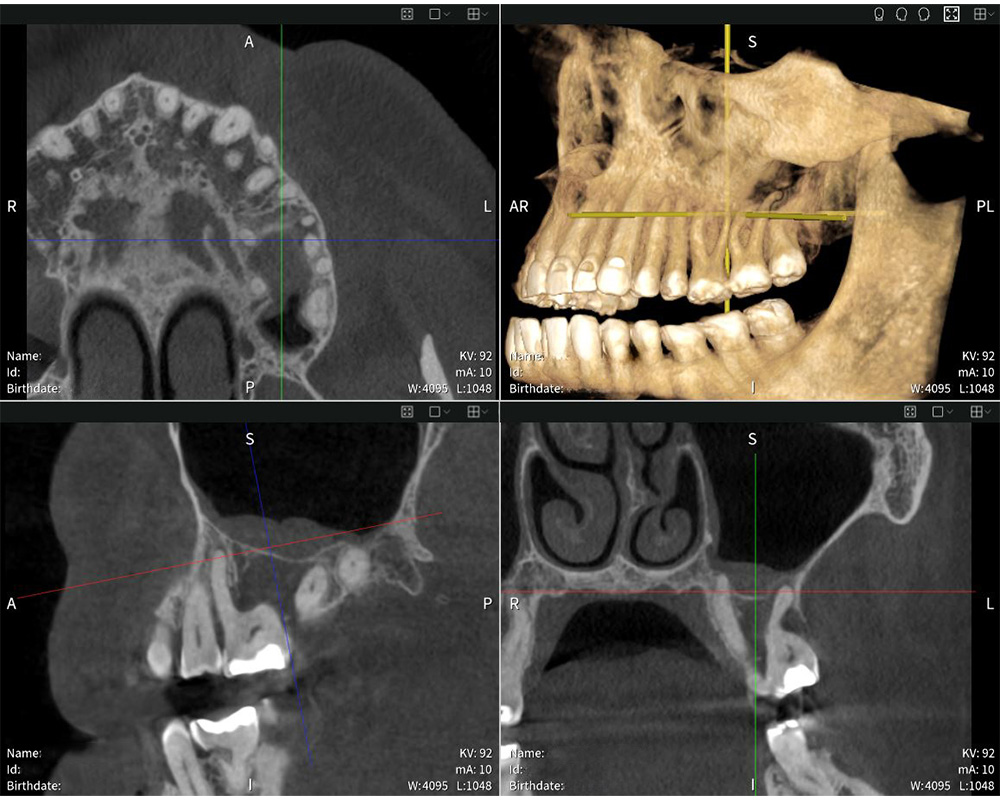

Seethrough Max setzt neue Maßstäbe in Sachen Benutzerfreundlichkeit. Das offene Design und die großzügigen Dimensionen bieten maximalen Komfort für Patient:innen und sorgen für eine besonders hohe Akzeptanz. Die Face-to-Face-Positionierung erleichtert zudem die Kommunikation zwischen Behandler:in und Patient:in. “Die Positionierung funktioniert ausgezeichnet. Ich schätze es, dass ich Patient:innen direkt gegenüberstehen und Blickkontakt halten kann. Das hilft mir, die optimale Patientenposition für einen präzisen Scan zu ermitteln”, so Dr med. dent. Mauro Amato. Ergänzend zur leistungsstarken Hardware sorgt Seethrough Studio für gestochen scharfe, detailreiche und unverzerrte Bilder. Ein fortschrittlicher Algorithmus zur Korrektur von Bewegungen verbessert die Bildqualität sowohl bei 3D- als auch bei 2D-Aufnahmen. Mit einem Field of View von bis zu 17 × 17 cm deckt Seethrough Max ein breites Anwendungsspektrum ab – von der Endodontie und Implantologie über die Oralchirurgie bis hin zur HNO – und das bei minimaler Strahlenbelastung. “Die Röntgenbilder überzeugen durch außergewöhnliche Schärfe und Detailtiefe, was eine exakte Diagnose und eine präzise Planung der Behandlung ermöglicht”, betont Dr med. dent. Mauro Amato.

Seethrough Flex vereint eine kompakte Bauweise mit Top-Bildqualität und steht dem größeren Pendant in nichts nach. Mit dem besten Verhältnis von Field of View zu Geräteabmessungen auf dem Markt bietet Seethrough Flex eine breite FOV-Abdeckung von bis zu 14 × 10 cm. Wie auch Seethrough Max profitiert das DVT-Gerät von der leistungsstarken Seethrough Studio Software, die die Bildqualität und digitale Arbeitsabläufe optimiert. “Die Software überzeugt durch ihre intuitive Bedienung. Die Benutzeroberfläche ist anwenderfreundlich, sodass ich schnell auf die benötigten Werkzeuge und Ansichten zugreifen kann””, erklärt Dr med. dent. Mauro Amato. Er ergänzt: “Die Software ermöglicht es mir, die Bilder aus verschiedenen Perspektiven zu betrachten und rasch und effizient die Antworten zu finden, die ich benötige”. Das Seethrough-Portfolio ist standardmäßig mit ioDent® vernetzt. Die fortschrittliche Onlineplattform von W&H vereint wichtige Patientendaten, nahtlose Kommunikation und zahlreiche nützliche Service- und Supportleistungen, die den Praxisalltag effizienter gestalten.